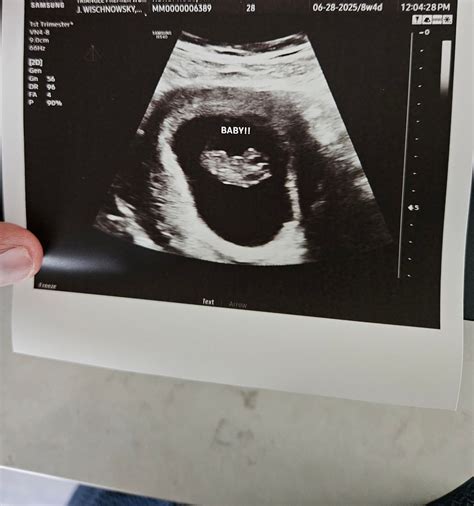

The nine-week ultrasound is typically performed between the eighth and tenth weeks of pregnancy. This scan is often transvaginal, providing clearer images of the uterus and the developing embryo. During this stage, the embryo is about the size of a grape, and several key developments are occurring.

• Embryo Size and Heartbeat: At nine weeks, the embryo is approximately 0.6 to 0.7 inches (15 to 18 millimeters) long. The heartbeat is usually visible and can be detected using Doppler ultrasound. The heart rate at this stage is typically between 120 and 160 beats per minute.

• Gestational Sac: The gestational sac, which houses the embryo and the amniotic fluid, is clearly visible. Its size and shape are assessed to confirm the pregnancy's viability.

• Crown-Rump Length (CRL): The measurement from the top of the embryo's head to its bottom. This measurement helps estimate the gestational age and due date.

• Fetal Pole: The fetal pole, which is the earliest visible sign of the embryo, should be clearly visible.

• Gestational Sac: The gestational sac's size and shape are assessed to confirm the pregnancy's viability.